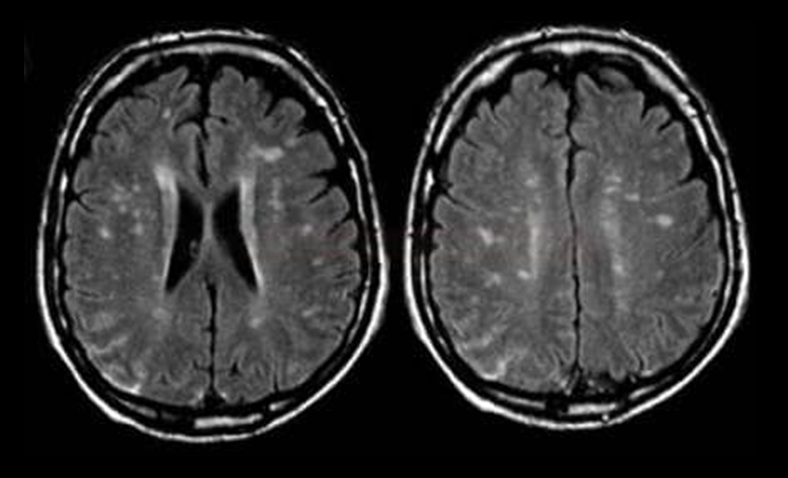

Fazekas grades. Лейкоареоз головного мозга мрт. Перивентрикулярный лейкоареоз мрт. Лейкоареоз Фазекас. Лейкоареоз на кт.

Fazekas grades. Лейкоареоз головного мозга мрт. Перивентрикулярный лейкоареоз мрт. Лейкоареоз Фазекас. Лейкоареоз на кт.

Fazekas grades. Лейкоареоз головного мозга мрт. Перивентрикулярный лейкоареоз мрт. Перивентрикулярный лейкоареоз головного мозга на кт. Лейкоареоз Fazekas 1 что это.

Fazekas grades. Лейкоареоз головного мозга мрт. Перивентрикулярный лейкоареоз мрт. Перивентрикулярный лейкоареоз головного мозга на кт. Лейкоареоз Fazekas 1 что это.

Fazekas grades. Лейкоареоз на кт. Лейкоареоз головного мозга мрт. Перивентрикулярный лейкоареоз. Перивентрикулярный лейкоареоз мрт.

Fazekas grades. Лейкоареоз на кт. Лейкоареоз головного мозга мрт. Перивентрикулярный лейкоареоз. Перивентрикулярный лейкоареоз мрт.